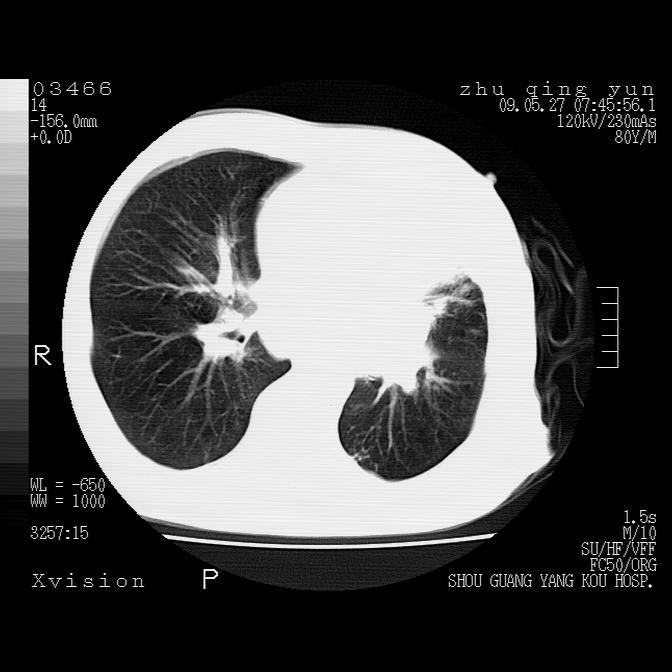

病人男性,年龄80,气喘来院,其他病史不太详细,1月前有过恶心,呕吐,在当地人民医院做过钡餐,诊断胃炎,

1)考虑左肺中央型肺癌并阻塞性肺炎,后下纵隔受侵伴纵隔淋巴结转移。2)双侧少量胸腔积液,胸膜增厚。3)心包积液。

左肺下叶见多发片状及结节状病灶,左肺基底段支气管闭塞,纵隔内见多发淋巴结肿大,纵隔向左侧移位,左侧胸廓变小。应该是左肺下叶中心型肺癌,纵隔淋巴结转移,左侧肺内转移,左肺基底段肺不张,阻塞性肺炎。

1)考虑左肺中央型肺癌并左肺下叶阻塞性肺炎、不张;左胸膜腔积液、心包积液、纵隔淋巴结转移;癌肿累及左心房。2)左心室大。冠状动脉壁钙化斑。